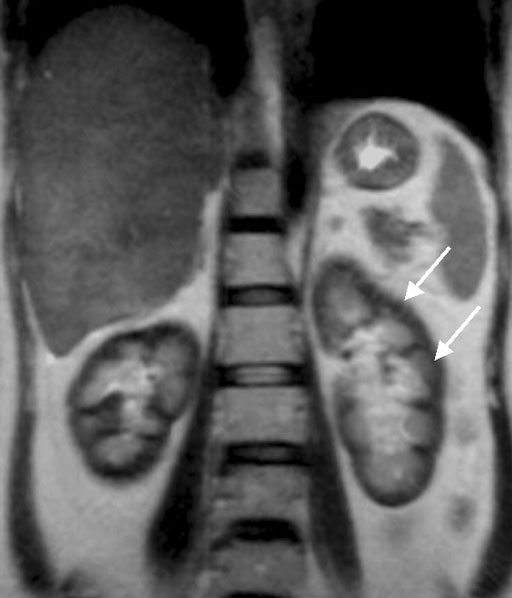

T1,T2強調画像ともにhemogiderin沈着を反映し、腎皮質が低信号を呈している(白矢印)

下大静脈内に血栓が同定される(白矢印)